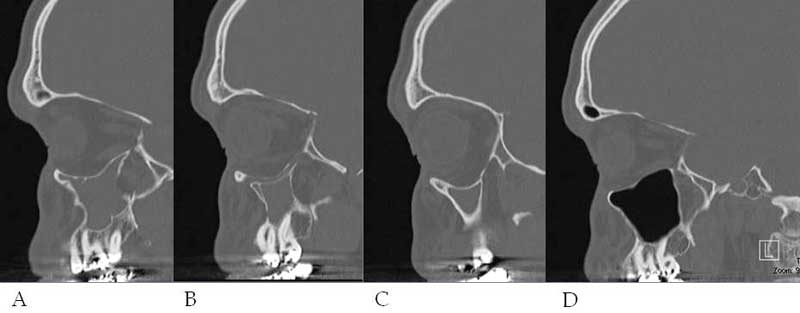

Figure 4: A, B, C. Sagittal CTs illustrating the inward bowing of all of the left maxillary sinus walls. D. Normal Right Side

Figure 4. (see caption)